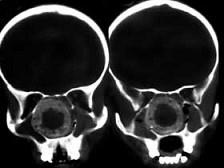

女,14岁,渐进性鼻塞2年余,右眼肿痛数月,CT如图所示,应诊断为 ( )

• A.筛骨骨化性纤维瘤

• B.筛骨骨肉瘤

• C.筛骨结核

• D.筛骨软骨瘤

• E.筛骨骨纤维瘤

答案: A